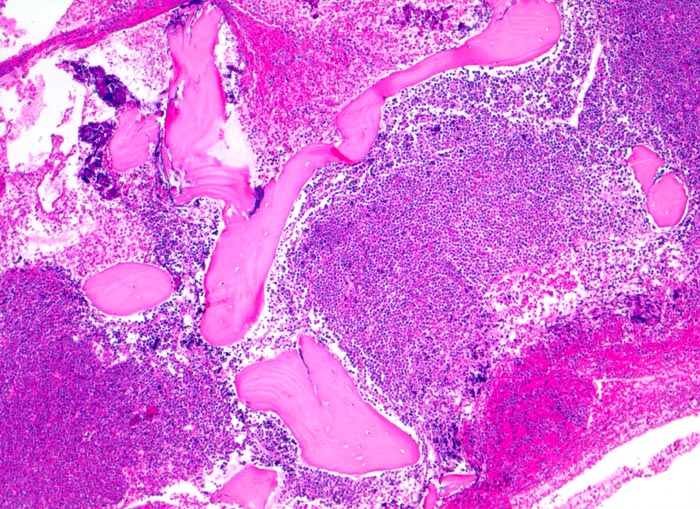

PathoPic – image database / PathoPic ID 4021 - Akute lymphatische Leukämie (ALL)

Akute lymphatische Leukämie (ALL)

Knochenmark, Beckenkamm

Verdrängung des Fettmarkes durch diffuse Tumorzellrasen ohne Zerstörung der Knochenbälkchen.

Histologie

50